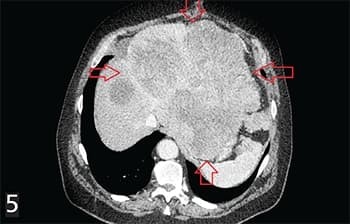

Рисунок 5. ГИСО верхней трети желудка. Состояние после секторальной резекции желудка. Прогрессирование: многоузловой опухолевый конгломерат с поражением печени, стенок желудка, 12-перстной кишки, левой ножки диафрагмы, брыжейки, сосудов с метастазами по брюшине, метастазами в мягких тканях передней брюшной стенки.В связи с этим рентгенологическое заключение и максимальное приближение к морфологической оценке на дооперационном этапе имеет большое значение в определении тактики ведения и лечения пациента.